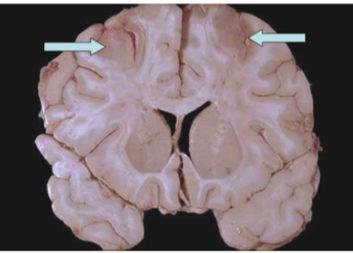

- Watershed infarcts: Wedge-shaped necrosis between ACA & MCA territories

- Laminar necrosis: Cell death in specific cortical layers (especially III, V, VI)